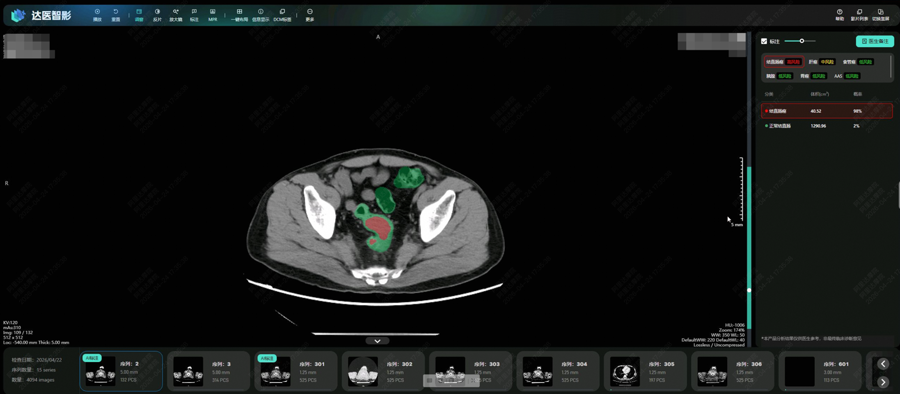

DAMO COCA模型自动识别结直肠癌风险

达摩院创新性地提出了用“平扫CT+AI”实现肠癌“机会性筛查”。平扫CT在国内广泛用于健康体检、创伤评估、腹痛排查,每年产生上亿份影像,如能从中检测肠癌病灶,就不用增加额外检查,顺带排查肠癌风险。然而,拍平扫CT时患者不做肠道准备,肠道内容物严重干扰平扫CT影像,医生判读难度极大。

为此,达摩院发挥在“平扫CT+AI”方面的多年技术积累,采用“先定位、后诊断”的两阶段深度学习架构和混合监督学习策略,更针对小于3厘米的早期肿瘤专门训练,使得AI模型能精细分割形态复杂的肠道部位并克服内容物干扰,检测可疑病灶。